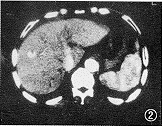

3.CT 可顯示遠端血管擴張,並有大量異常的末梢分支,並能排除引起低氧血症的其他原因,如肺氣腫或肺纖維化。但上述改變均無特異性。現有人提出利用三維重建螺鏇CT 進行肺血管影像重建可能是將來確定的熱點,在區分肉眼可見的動-靜脈異常方面與選擇性肺血管造影有相同的準確率。

5 、CT表現 HPS患者胸部CT可顯示肺遠端血管擴張,有大量異常的末梢分支,可提示HPS的存在,但無特異性。胸部CT排除低氧血症的其他原因:肺氣腫、肺纖維化等。薄層CT掃描顯示HPS的肺段動脈直徑與鄰近支氣管直徑的比率明顯大於無低氧血症的肝硬化患者。